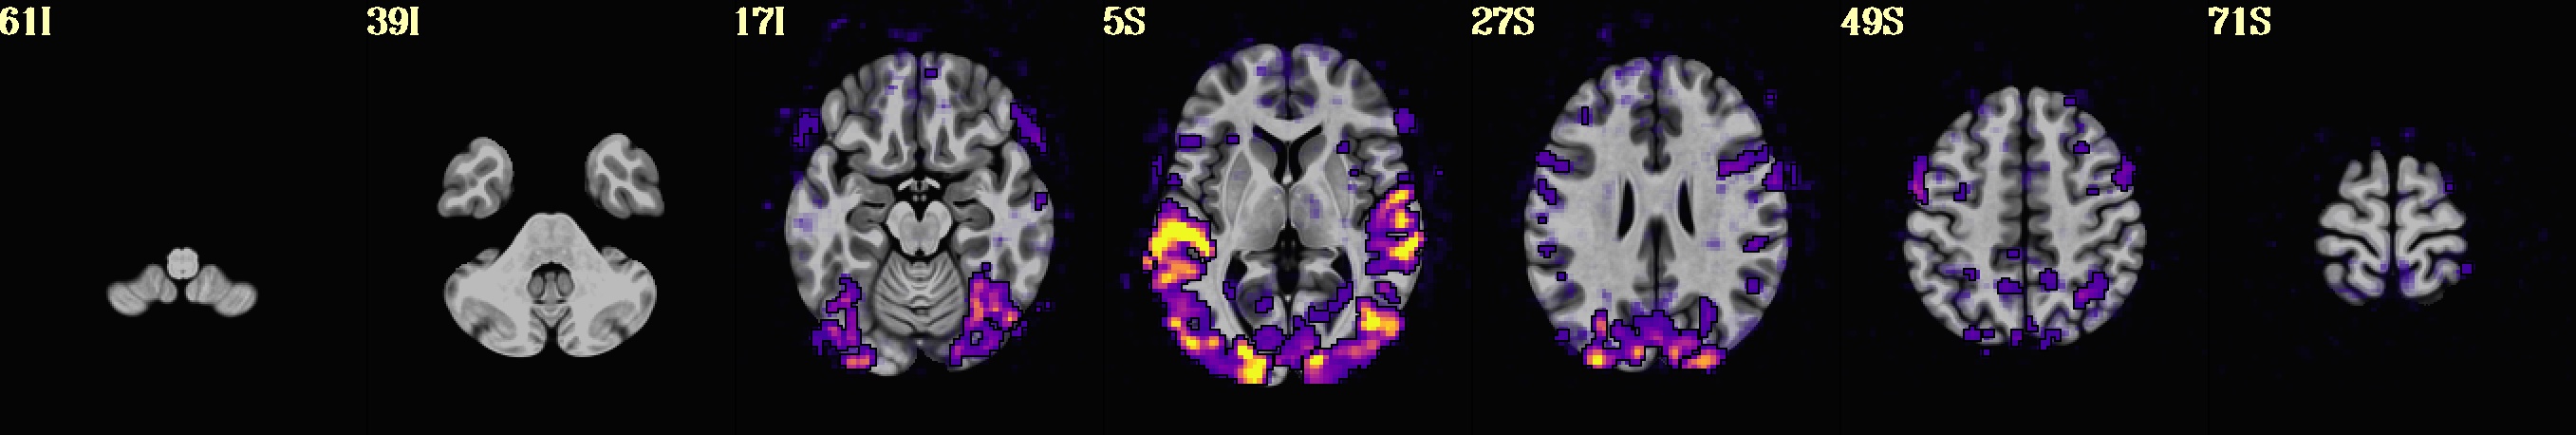

But I understand about wanting to preserve the sizes of a given row, too. If you would like to have the relative size of each panel preserved rather than stretched, you could basically ask 2dcat to pre-pad each image before gluing them together with -respad_in ...

In the example case I have made here, the pixel dimensions of the 3 images were: 3584x512 , 2614x512 and 2614x512. (I found this out by using eog .. to view them from the command line, then in the GUI viewer that pops up I right-clicked and selected "Properties" to see the image size.) So, I figured if I pre-padded each image to the dimensions of the largest, that should preserve the relative size. It is not required to be the dimensions of the largest image, I just thought that would be convenient

So, here is my command to pre-pad

2dcat                                                                        \

-nx         1                                                            \

-ny         3                                                            \

-gap        5                                                            \

-gap_col    100 100 200                                                  \

-respad_in  3584 512                                                     \

-prefix     IMG_respad.jpg                                               \

img_row.*

... which produced:

If I hadn't use that image, the program will pre-expand each image to have rectangularity, so that this:

-prefix     IMG_respad.jpg img_row.*

produces:

Hope that is useful.